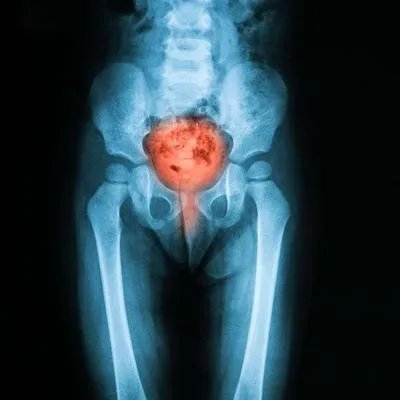

尺骨撞击综合征主要由尺骨茎突、月骨和尺骨三角的撞击以及手腕疼痛和运动受限的症状引起。尺骨缩短通常用于外科治疗,目的是缓解疼痛和改善手腕运动。

对于尺骨撞击综合征,一般情况,可以选择保守治疗或手术治疗。手术治疗一般在保守治疗效果不明显的情况下进行,疼痛和运动受限症状影响了患者的正常生活和工作。如果患者感到非常强烈和无法忍受的疼痛,可以考虑接受外科治疗。手术治疗主要是进行斜骨截骨术和尺骨缩短术,但在进行该手术之前,需要确定患者是否适合该手术。虽然有些患者尺骨有囊性异常改变,但月骨也有囊性改变,但位置靠近桡侧,而不是尺骨受撞击的位置。此类患者在随访后可能导致术后疼痛加重和月骨坏死,因此,患者和医生应谨慎处理此类疾病,并在手术前做好检查,明确诊断和手术指征。